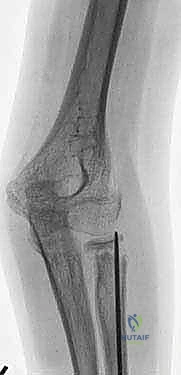

كسر عنق الكعبرة من النوع الثاني (Salter-Harris type II) مع إزاحة واضحة في منطقة الكردوس بالنسبة للمشاشة، وهي حالة تتطلب تقييماً دقيقاً من قبل خبير مثل الأستاذ الدكتور محمد هطيف.

كسر عنق الكعبرة من النوع الأول (Salter-Harris type I)، حيث يمر خط الكسر بالكامل عبر صفيحة النمو، وقد يكون خفياً في صور الأشعة السينية الأولية ويحتاج لعين خبيرة لاكتشافه.